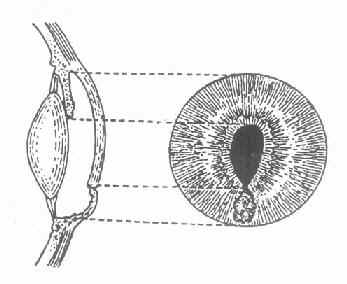

3.虹膜脱出(irisprolapse)角膜溃疡穿孔时,由于房水流出,虹膜可脱出于穿孔处,瞳孔失去圆形,呈瓜子状,其尖端朝向虹膜脱出处,(图6-3)此时眼压降低,眼球变软。在愈合过程中,可出现以下几种情况。

图6-3 虹膜局部脱出的正面与侧面示意图

(1)粘连性角膜白斑(adherentcorneal leucoma )虹膜脱出后,在虹膜表面上很快产生纤维蛋白性渗出物,凝聚在穿孔处及脱出的虹膜上,并将溃疡边缘与虹膜脱出部分固定起来,不使前房与外界相通,前房逐渐恢复。溃疡愈合后,在角膜瘢痕组织中,夹杂有脱出的虹膜组织。这种角膜瘢痕叫粘连性角膜白斑。(图6-4)

图6-4 粘连性角膜白斑